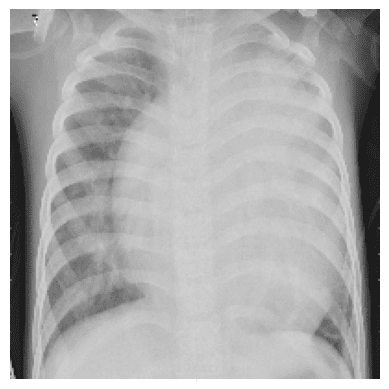

التعرف على ال (Pneumonia) -مرض رئوي- من خلال صور الاشعة

في هذا المشروع قمت بتصميم وتدريب شبكة عصبية تلافيفية (CNN) مخصصة لاكتشاف الإصابة بالتهاب الرئة من صور الأشعة الصدرية (Chest X-Rays).

بلغت دقة عاليّة (Precision تصل إلى 95٪) في تمييز الحالات الإيجابية بدقة من بين الصور المتاحة.

تقديم نموذج قوي ودقيق يمكن استخدامه للمساعدة في التشخيص المبكر للحالات المحتملة من الالتهاب الرئوي، مما يسهم في تحسين السرعة والدقة في عملية الفحص الطبي.